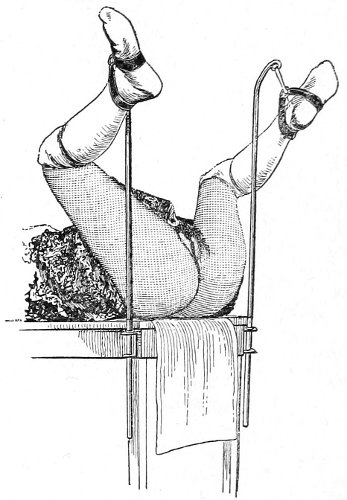

Vaginal and Bimanual Examination.—Having examined and noted the condition of the external genitals, the physician should next proceed to examine the vagina. The index finger of the right or the left hand should be gently introduced into the vagina. The condition of the vaginal walls, and the direction, consistency, form, etc. of the vaginal cervix, may be determined. The shape and size of the os uteri should be noted. The ulnar edge and the tips of the fingers of the other hand should then be placed upon the abdomen, immediately above the symphysis pubis, and gently pressed backward and downward toward the vaginal finger 24 (Fig. 2). In this way the various pelvic organs, the uterus, Fallopian tubes, ovaries, and ureters, may be palpated between the two hands, and their position, size, shape, and consistency may be determined. Such an examination is, of course, made much more easily in a thin woman than in a fat one. A thin woman a few weeks after labor may be examined most easily, on account of the relaxation of the abdominal and vaginal walls.

Fig. 2.—Bimanual examination.

This is called the bimanual method of examination, and the student will find that as he acquires practice in this method he will gradually depend less upon examination by the uterine sound and the speculum, and will rely altogether upon his sense of touch, his ability to palpate.

It matters not which hand be used in making the vaginal examination. It will, however, be found that the hand that is used the more frequently will become the more proficient.